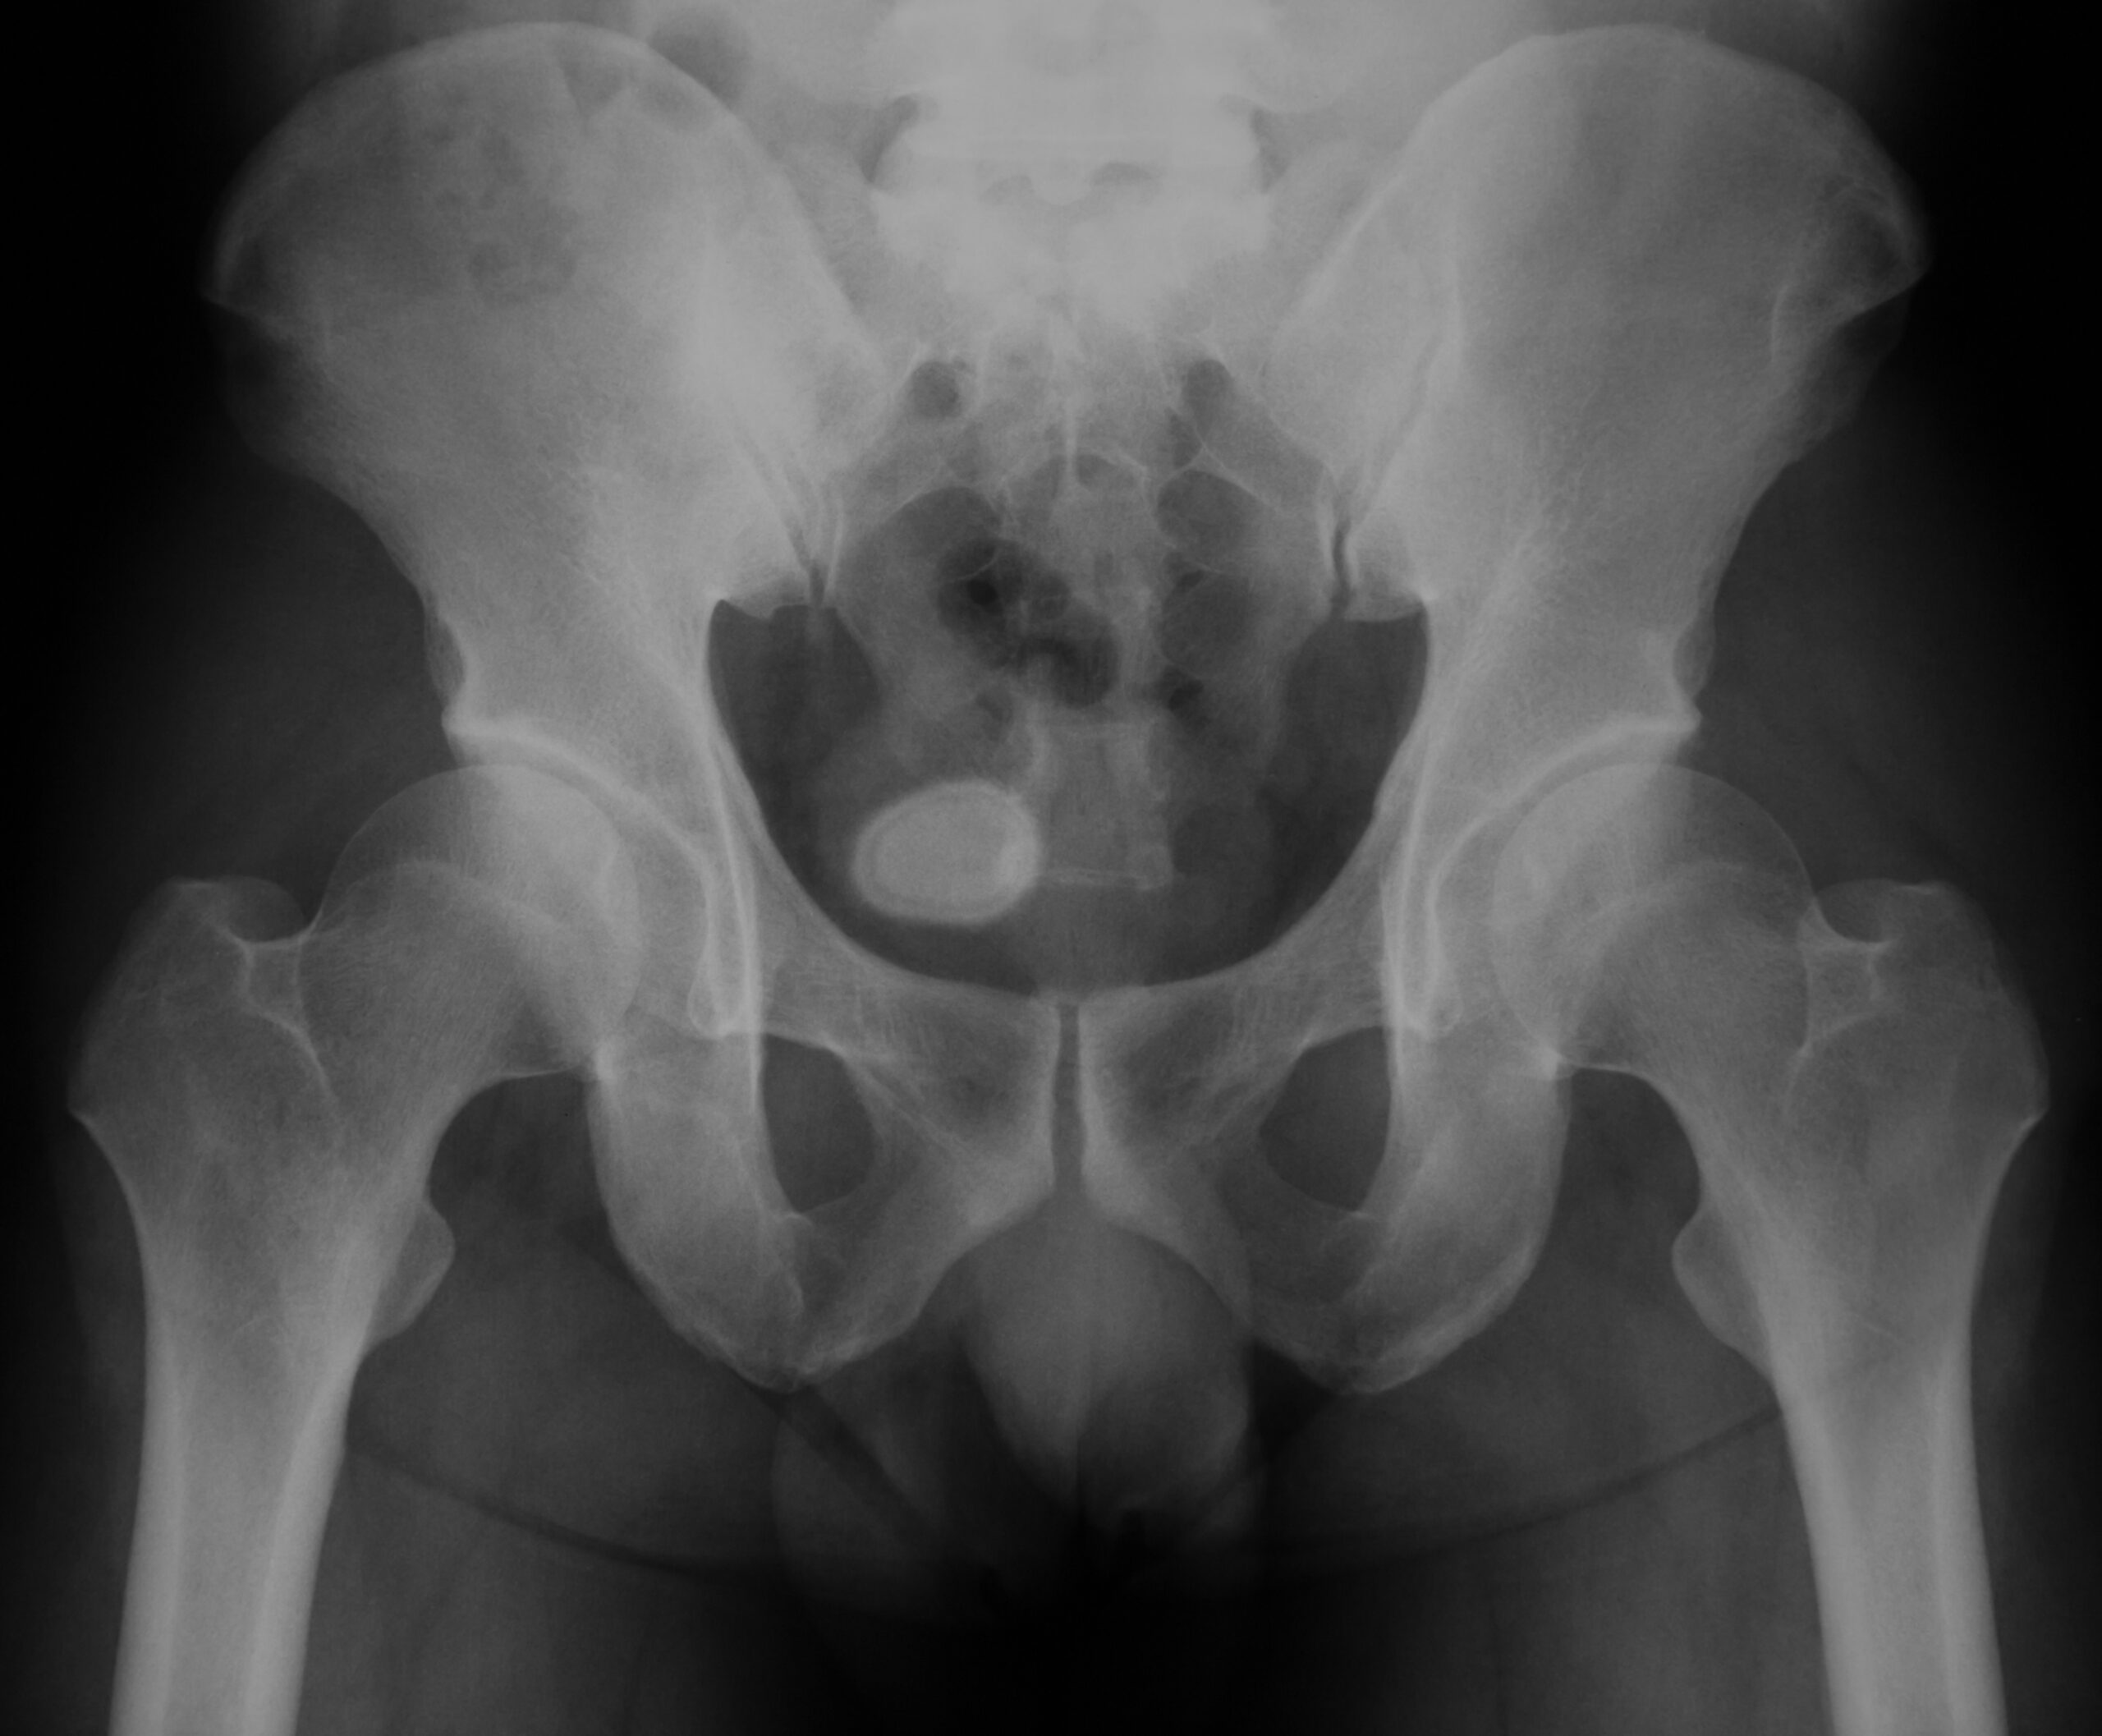

Si usted tiene síntomas, consulte al médico de inmediato. El médico le hará un examen físico. Presionará su estómago para evaluar si tiene dolor. En pacientes hombres, el médico puede hacer un examen rectal para revisar la próstata. Las pruebas adicionales incluyen:

• imágenes de diagnóstico de la pelvis (tomografía computarizada, radiografía, ecografía);

• imágenes de diagnóstico del tracto urinario (tomografía computarizada), que pueden incluir material de contraste, una tinta especial que se inyecta en las venas para visibilizar los cálculos;